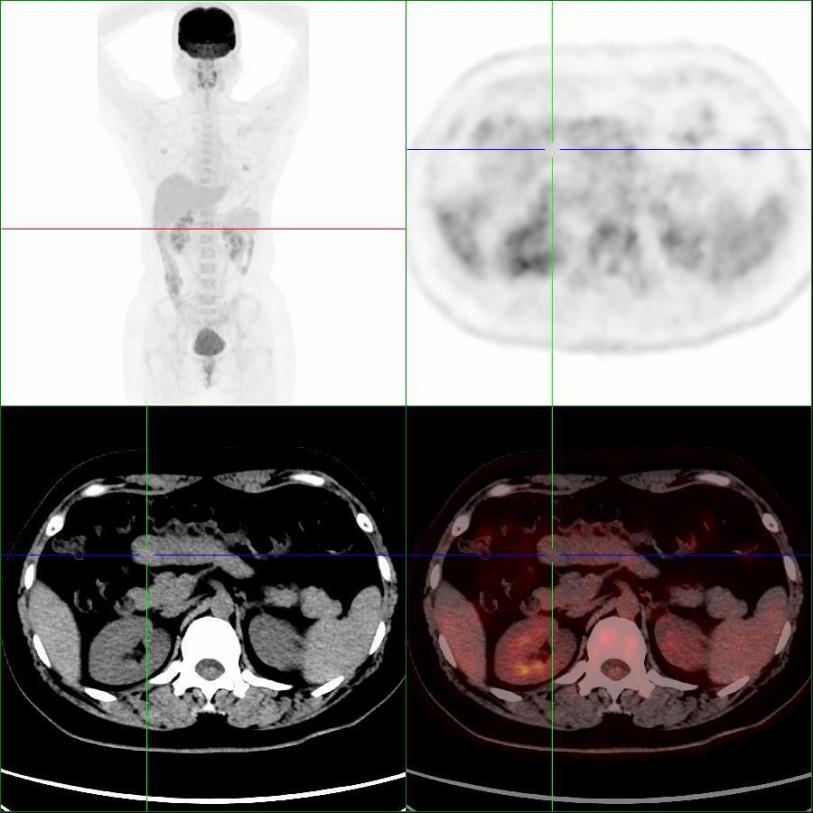

患者完善PET/CT檢查,小腸結(jié)節(jié)未見明顯代謝異常,考慮良性病變(圖2)。

圖2,PET/CT示小腸結(jié)節(jié)(十字線交叉處),呈低代謝表現(xiàn)

患者因有“惡性黑色素瘤”病史,對良性病變的診斷存在疑慮,遂進行了小腸結(jié)節(jié)的手術(shù),行腹腔鏡探查+小腸腫瘤切除術(shù),術(shù)后病理考慮“異位胰腺”。

本例患者有"右胸壁惡性黑色素瘤"手術(shù)病史,且增強CT懷疑“神經(jīng)內(nèi)分泌腫瘤”,行PET/CT檢查目的是為了進一步明確分期,指導(dǎo)后續(xù)治療。PET/CT表現(xiàn)為低代謝,提示良性病變,最終得到病理證實。PET/CT是分子影像學(xué)利器,能夠從代謝的角度提供信息,反映細胞活躍程度,為診斷帶來新的思路。惡性腫瘤或炎癥病變細胞葡萄糖酵解能力往往高于正常組織細胞,會大量積聚18F-FDG,從而被PET敏感地捕捉到。當(dāng)PET顯像為“陰性”顯像時,說明細胞代謝不活躍,更傾向良性病變。